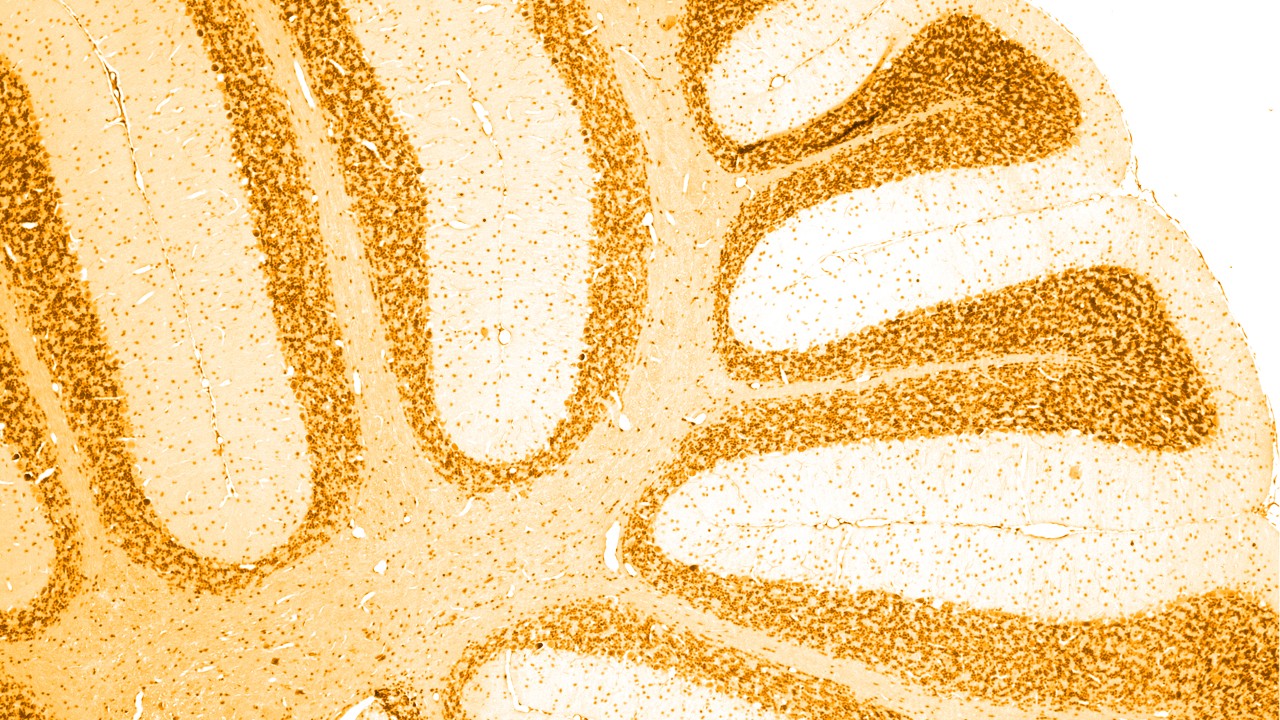

Los trastornos neurológicos son enfermedades del sistema nervioso central y periférico. En otras palabras, el cerebro, la médula espinal, los nervios y los músculos que regulan y coordinan la actividad corporal.

Hay varias causas diferentes de demencia, de las cuales la más común es la enfermedad de Alzheimer, relacionada con la acumulación de "placas amiloides" y "ovillos neurofibrilares", poco habituales en el cerebro. Otros tipos de demencia también consisten en una acumulación anormal de la proteína tau en el cerebro; a nivel genérico, se denominan "tauopatías".